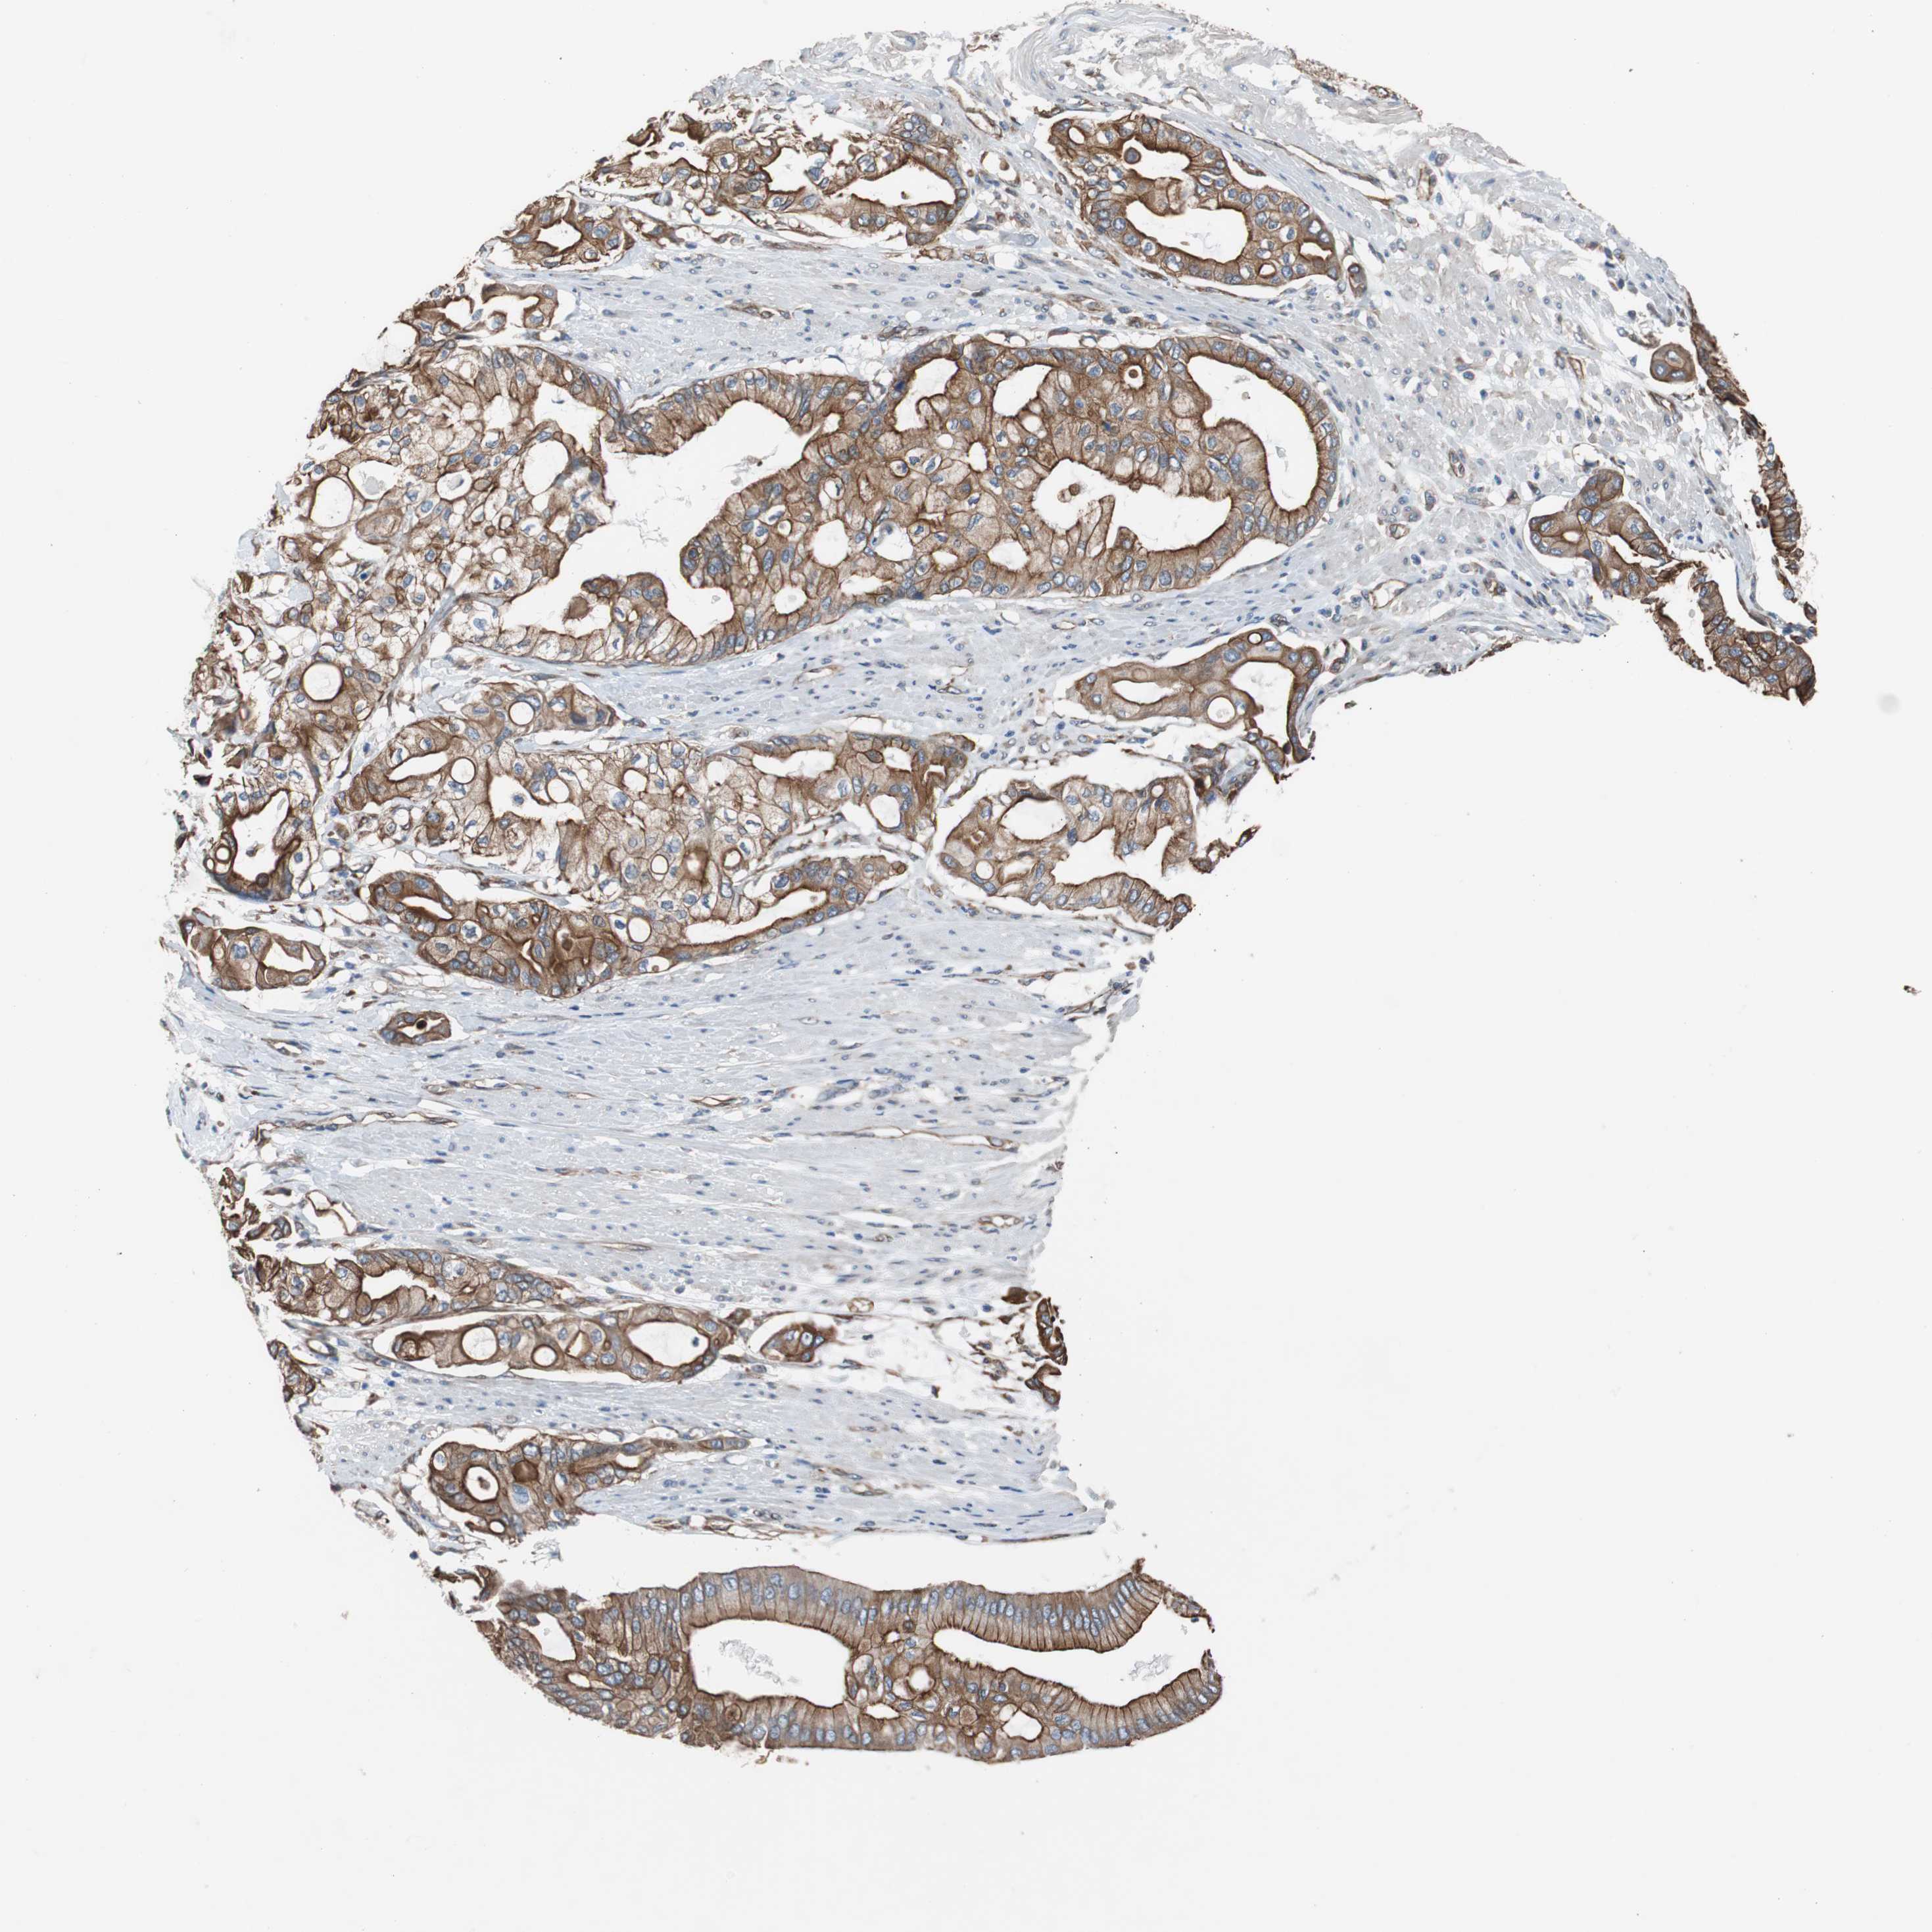

PANCREATIC CANCER - Protein expressioni

A mouse-over function shows sample information and annotation data. Click on an image to view it in a full screen mode. Samples can be filtered based on level of antibody staining by selecting one or several of the following categories: high, medium, low and not detected. The assay and annotation is described here.

Note that samples used for immunohistochemistry by the Human Protein Atlas do not correspond to samples in the TCGA dataset.

Antibody stainingi

Antibody staining in the annotated cell types in the current human tissue is reported as not detected, low, medium, or high, based on conventional immunohistochemistry profiling in selected tissues. This score is based on the combination of the staining intensity and fraction of stained cells.

Each image is clickable and will lead to virtual microscopy that enables deeper exploration of all samples and also displays staining intensity scores, fraction scores and subcellular localization as well as patient and tissue information for each sample.

Antibody HPA007119

Staining

High

Medium

Low

Not detected

Intensity

Strong

Moderate

Weak

Negative

Quantity

>75%

75%-25%

<25%

None

Location

Nuclear

Cytoplasmic/membranous

Cytoplasmic/membranous,nuclear

Adenocarcinoma, NOS

Adenocarcinoma, metastatic, NOS